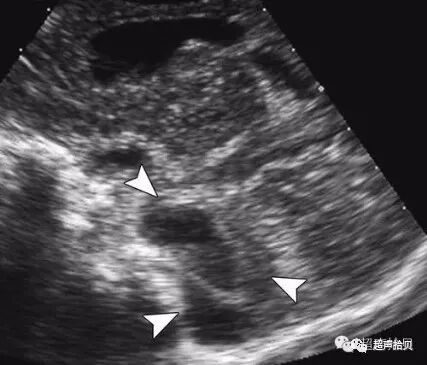

图2:冠状超声图显示位于后颅窝蛛网膜囊肿

1)脑内脑中线第三脑室后方或颅后窝内圆形、椭圆形或不规则形囊性暗区,壁薄光滑。

2)与侧脑室等不相通。小脑蚓部大小正常;